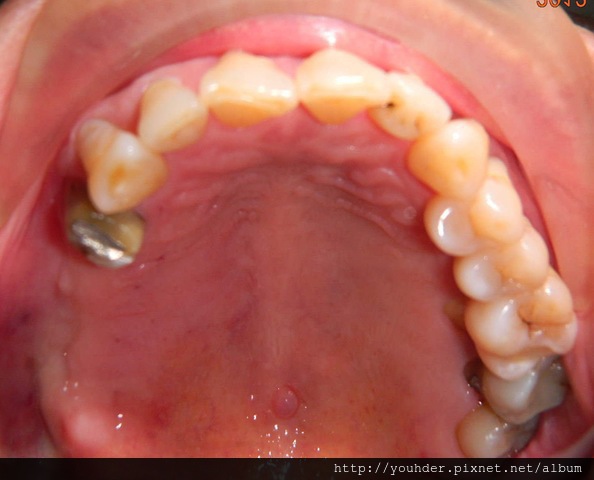

患者A先生

上顎 正面 下顎

患者B小姐

以上兩位患者口內狀況非常複雜,要制定一個好的治療計畫,

不只要考慮到患者的牙齒條件,

還要顧及患者意願、時間、金錢、評估可獲得的結果等等。

所以像這類型的Case 醫師通常在初步的溝通後會先做出一兩個不同的治療計畫,

再和患者解釋,了解患者接受程度。